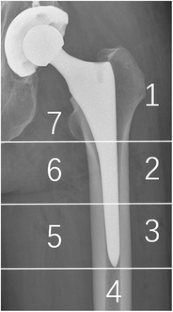

In the control group patients showed significant loss of periprosthetic BMD in ROIs 1, 2, 6, and 7 throughout the study period. The loss of BMD in ROIs 3 and 5 was only significantly observed at three months follow-up and recovered thereafter. There were no significant detected changes of BMD in ROI 4. In the Simvastatin group, the percentage of BMD loss was significantly less (P < 0.05) in ROI 1, 2, 6 and 7 throughout the study period than the control group. The percentage of BMD loss were significant observed in ROI 3 and 5 at three months follow-up, which were also significantly less (P < 0.05) than in the control group. A slight gain of BMD was measured in ROI 4 at 12 months follow-up (1.419%, P < 0.05).

Fig. 1